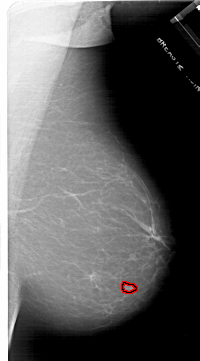

A_1716_1.LEFT_MLO

LEFT_MLO LINES 6541 PIXELS_PER_LINE 4081 BITS_PER_PIXEL 12 RESOLUTION 43.5 NON_OVERLAY

FILE: A_1716_1.RIGHT_MLO.OVERLAY

TOTAL_ABNORMALITIES 1

ABNORMALITY 1

LESION_TYPE MASS SHAPE LOBULATED MARGINS MICROLOBULATED

ASSESSMENT 4

SUBTLETY 4

PATHOLOGY BENIGN

TOTAL_OUTLINES 1

BOUNDARY